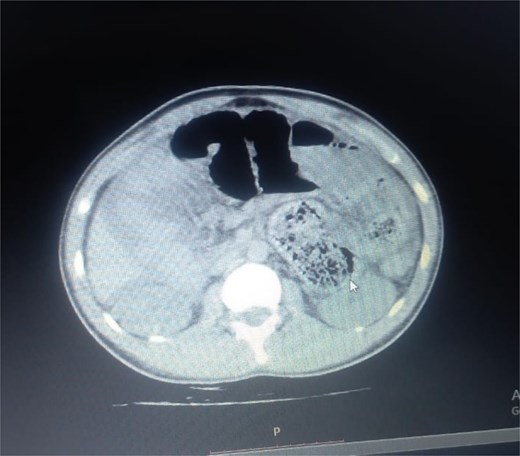

Initial radiographic evaluation with a plain abdominal X-ray confirmed the clinical suspicion of acute intestinal obstruction, demonstrating multiple air-fluid levels and diffuse small bowel dilatation (Fig. 1). To further delineate the underlying etiology, a contrast-enhanced computed tomography (CECT) scan was performed; providing critical diagnostic information it revealed, in the right iliac fossa, a striking encapsulation of the small intestine loops within a sac-like membrane, accompanied by ascites. This constellation of findings formed a pathognomonic cocoon-like structure (Fig. 2). Furthermore, the CECT identified a concurrent gut malrotation, evidenced by a left-sided displacement of the colon (Fig. 3). Laboratory findings showed an elevated total leukocyte count (TLC) of 21 000, indicative of inflammation, while other parameters were within normal limits. The patient underwent an exploratory laparotomy. Intraoperatively, the abdominal viscera were encased within a thick fibrous membrane (Fig. 4), containing ascitic fluid. The membrane was incised, adhesiolysis was performed, and the entrapped small bowel loops were released, and then a kink in the small intestine causing obstruction was identified and corrected. Additionally, the appendix was found to be secondarily involved in the encapsulating process. It was encased in the dense fibrocollagenous membrane, forming an inflammatory mass consistent with chronic serositis and localized fibrosis, rather than a classic acute appendicular phlegmon. Based on this intraoperative assessment that the mass was a manifestation of the cocoon’s chronic inflammation, a simple appendectomy was performed instead of a more extensive right hemicolectomy. This procedure was necessary to achieve complete release of the entrapped bowel, remove this localized inflammatory focus, and obtain a specimen for histopathology to definitively rule out a primary appendiceal pathology as a secondary cause of the peritonitis. Furthermore, ascitic fluid analysis showed no bacterial or mycobacterial growth, ruling out tuberculosis and the histopathological examination confirmed the fibrocollagenous nature of the membrane. The patient recovered well postoperatively and was discharged on the sixth day with advice for a follow-up after 2 weeks. At the follow-up visit, he reported no symptoms, and abdominal imaging confirmed the absence of obstruction. Histology further confirmed the benign fibrous nature of the membrane, with no signs of malignancy.

Intraoperative findings of idiopathic Sclerosing encapsulating peritonitis. The image displays the abdominal viscera entirely encased within a smooth, thick, cocoon-like sac, consistent with abdominal cocoon syndrome. The whitish, glistening appearance of the membrane is characteristic of its dense, fibrocollagenous composition, which was later confirmed by histopathology.